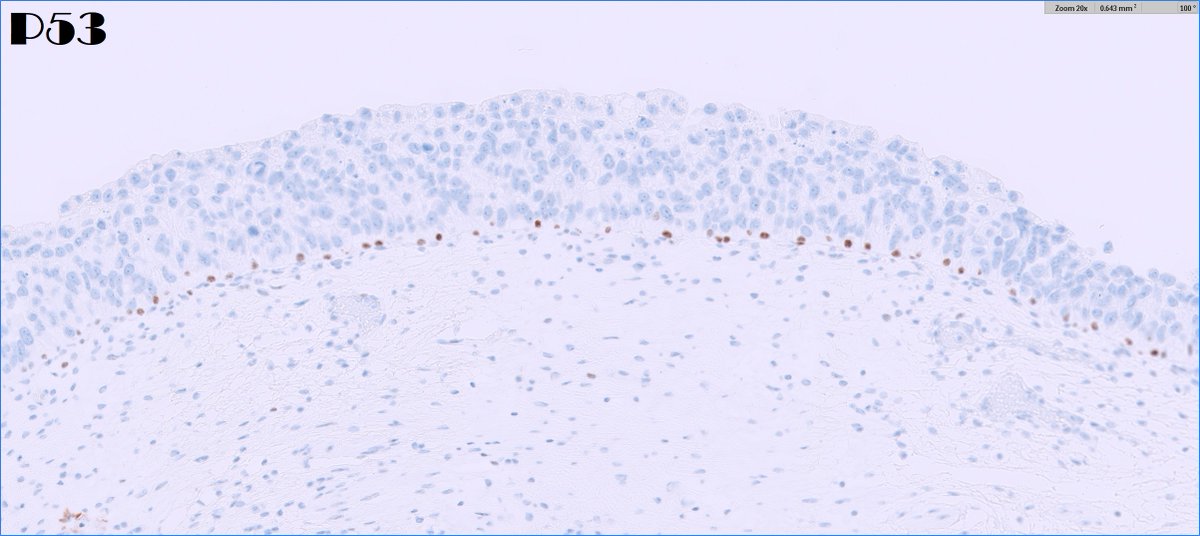

*** Case of the Month *** Bladder lesion in an 80 yr old female patient Contributors : Ronniel Morais Albuquerque Daniel Athanazio FB: GU Pathology Society IG: gu_pathology_society LinkedIN: GUPS Society Bluesky: https://t.co/1hR9PHdTaG

https://t.co/ijDfT9Juld